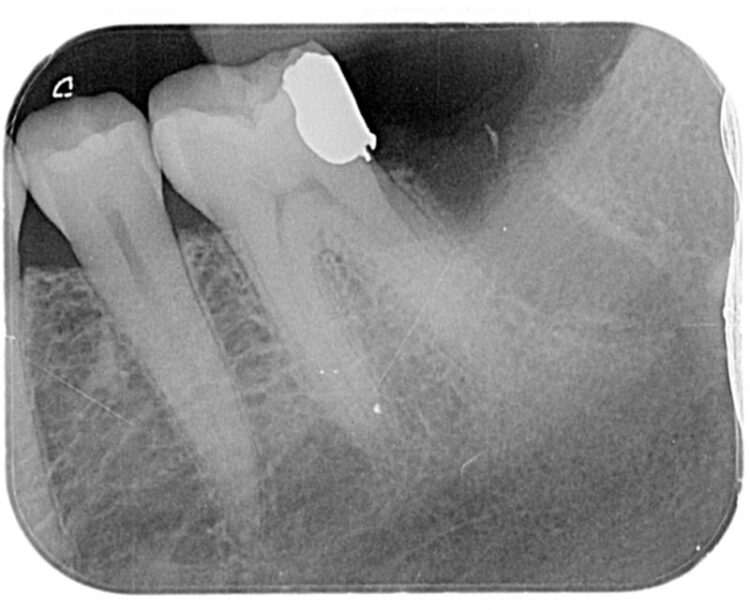

This 53-year-old, medically fit and well male patient attended complaining of pain and tenderness from his lower left second molar. Clinical and radiographic examination showed this molar tooth to be broken down and unrestorable. It was decided that this tooth required extracting and the patient was keen to replace this gap with a dental implant.

Following three months of healing, a CBCT scan was taken to assess bone dimensions and proximity of nearby anatomical landmarks, namely the inferior dental nerve and the lingual undercut of the mandible.